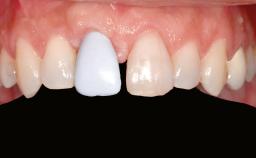

Replacement of Multiple Teeth in a Partially Dentate Posterior Mandible with a Fixed Dental Prosthesis Using a Flapless Approach

Her chief complaint was her inability to masticate efficiently due to the recent loss of her mandibular second premolars and first molars bilaterally. She expressed a desire for fixed prostheses in the shortest possible time due to her advanced age, requesting that replacement teeth should look as natural as possible. She was otherwise comfortable and not experiencing any symptoms from her teeth.